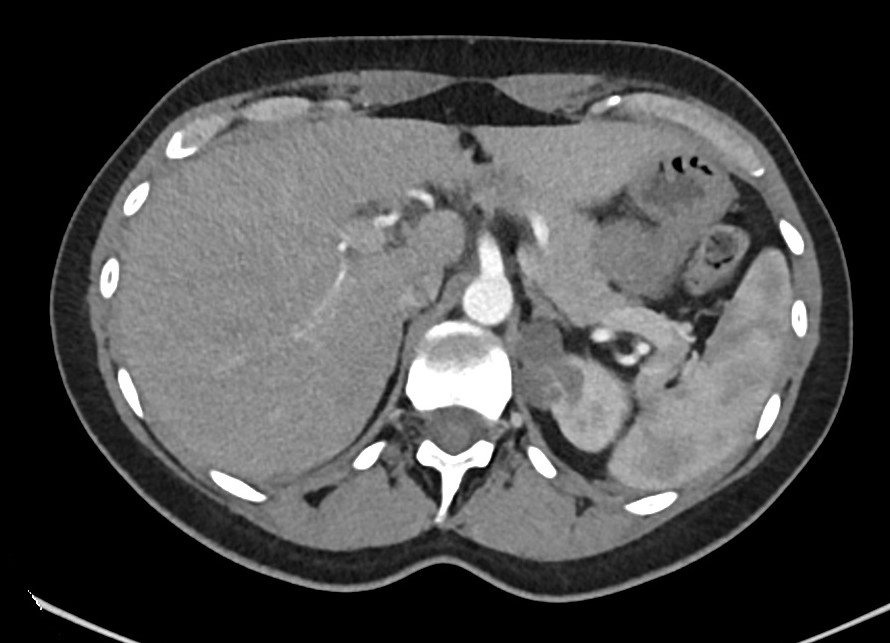

Hallazgos ecográficos

Ecografía abdominal en el Centro de Atención Primaria: lesión quística anecoica de 80 x 46 x 54 mm ubicada en mesogastrio. Quiste complejo de 30 x 30 mm, de paredes y septos engrosados, ubicado en polo superior del riñón izquierdo.

Juicio clínico: hallazgos de una lesión quística en mesogastrio y otra lesión quística compleja en el polo superior del riñón izquierdo.

Tomografía computarizada de abdomen: lesión quística en flanco izquierdo sin evidente dependencia con ningún órgano y de probable origen mesentérico o mesenquimal, posible linfangioma. Cambios inflamatorios periféricos y contenido heterogéneo post-sangrado. Quiste renal izquierdo Bosniak tipo III.

Resonancia magnética intestinal y renal: lesión mesentérica de 7,3 cm compatible con linfangioma quístico versus quiste dermoide. Quiste cortical en el polo superior del riñón izquierdo Bosniak III.